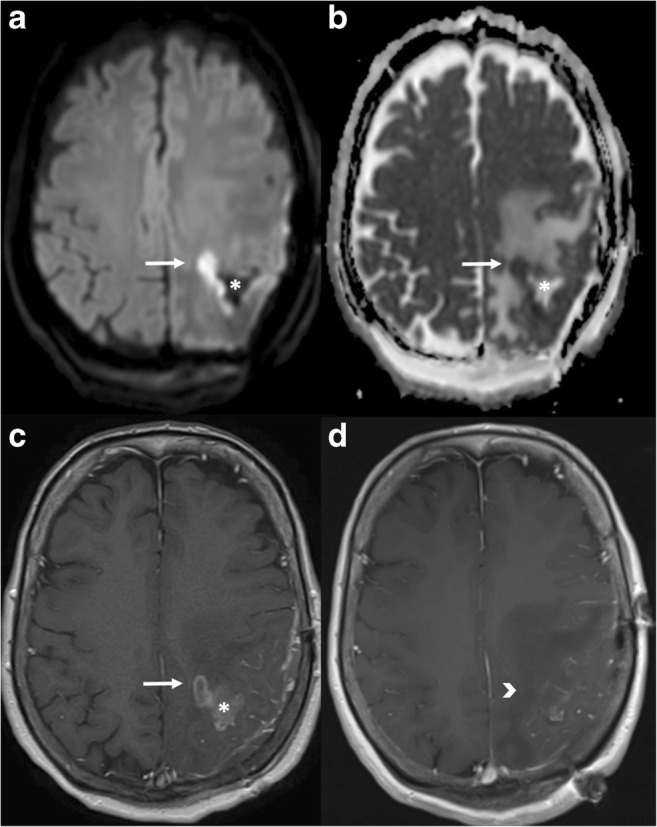

Fig. 5.

Primary CNS lymphoma. Left frontal periventricular lesion showing prominent diffusion restriction, presenting with hyperintensity on DWI (a), low ADC value (b) and mild hyperintensity on T2WI (c), all typical features of this type of hypercellular tumour. T1WI post gadolinium (d) shows homogeneous and intense contrast enhancement

Fig. 7.

Post-surgical ischaemia. Immediate follow-up MRI in a patient who underwent surgery for resection of a suspicious enhancing mass. In the medial aspect of the resection cavity (asterisk) there is an enhancing area on the T1 post-contrast sequence (c, arrow). This finding alone could represent residual tumour, but the presence of restricted diffusion with high signal on DWI (a) and a low ADC value (b) meant that a small area of peri-surgical ischaemia was more likely. Three-month follow-up T1 post-gadolinium MRI (d) shows absence of enhancement in the same region (arrowhead), confirming this diagnosis